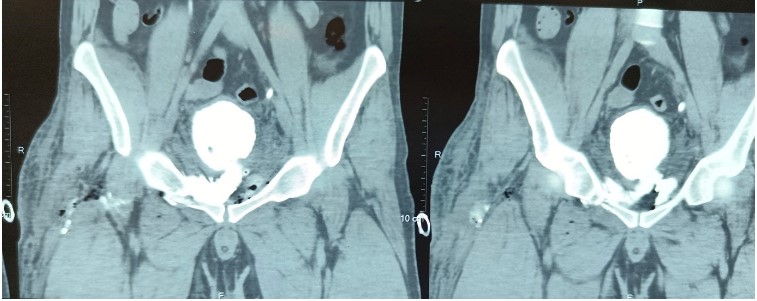

Our index case is a 28-year-old male who fell from a height of approximately 2 stories resulting in a closed pelvic fracture. The patient presented to us within 12 hours of injury with a right thigh wound caused by a penetrating injury caused by a metal rod. On presentation, he had an approximately 2 cm by 2.5 cm lacerated wound over the lateral aspect of the right thigh with a serous fluid like discharge from the wound site. On foley’s catheterisation, 400 millilitres of clear urine was drained. Ultrasound revealed normal kidneys bilaterally with a partially distended bladder as well as peri vesical collection. Computed tomography (CT) scan revealed right pubic ramus fracture with multiple displaced fragments as well as a left acetabular fracture. On delayed phase, contrast extravasation was noted on the right side of the bladder neck via a defect measuring 10 mm x 15 mm. The contrast was seen extending along the space of Retzius as well as along ilio-psoas and obturator internus muscles as well as soft tissue spaces of the thigh. After 3 days of conservation and drainage via catheter, a diagnostic cystoscopy was performed and revealed a zone of erythema at the left superolateral surface of the bladder approximately 2 cm from the bladder neck. However, no obvious rent or tear was seen. Findings were confirmed after performing an on table cystogram with contrast and C-arm guidance. The patient was discharged thereafter with foleys catheter in situ for 2 weeks and later given a successful foleys free trial as well as successful healing of the right thigh wound.

Figure 3: CT image depicting the path of the fistulous tract.